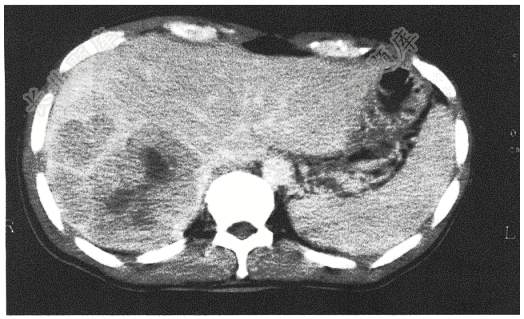

- 简答题患者,男性,65岁,腹胀、乏力2月,请结合患者病情,读取相应影像学检查,并答出X线检查类型、投照体位、征象以及诊断